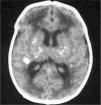

Exámenes complementarios: analítica sangre: 17.500 leucocitos (70 % granulocitos, 10 % linfocitos); hemoglobina, 13g/l; plaquetas, 153.000/μl; proteína C reactiva, 13mg/l; transaminasa glutámico oxalacética (GOT), transaminasa glutámico pirúvica (GPT), calcio, fósforo, amonio, láctico, hormona paratiroidea (PTH) y perfil tiroideo sin alteraciones. Los aminoácidos y los ácidos orgánicos en orina son normales. El citomegalovirus (CMV) en orina es negativo. Serologías toxoplasma y rubéola IgG+/IgM–. Lúes, herpes, parvovirus B19 y CMV IgG–/IgM–. Ecografía cerebral (fig. 2): calcificaciones múltiples en ambos hemisferios con afectación talámica. TC cerebral con contraste (fig. 3): calcificaciones múltiples en ambos hemisferios afectando sustancia blanca subcortical y sustancia gris profunda. Punción lumbar: linfocitosis y aumento de IFN-α y de pterinas, por lo que se estableció el diagnóstico de síndrome de Aicardi-Goutiéres. Se envió muestra para estudio genético.

En el LCR se objetiva linfocitosis, moderada hiperproteinorraquia y elevación de IFN-α. que estará más aumentado que a nivel sistémico3. El IFN-α interviene en los mecanismos de defensa antivirales y antitumorales5 y no se detecta en sangre de sujetos sanos. Se ha descrito elevado en infecciones del sistema nervioso central como encefalitis herpética o por virus de la inmunodeficiencia humana (VIH), en meningitis virales (enterovirus, parotiditis, virus varicela-zóster y rubéola congénita) y en una única entidad no infecciosa como el neurolupus. No atraviesa la barrera hematoencefálica, por lo que si está aumentado en el LCR, la producción es intratecal por infección o, como en nuestro caso, por mala regulación debido a la mutación de su gen. El aumento de IFN-α como mecanismo proinflamatorio da lugar a una vasculitis y ésta a las calcificaciones cerebrales1 que se objetivan en la TC craneal: calcificaciones en ganglios de la base que suelen ser bilaterales y simétricas, leucodistrofia y atrofia periventricular y periférico cerebral6.